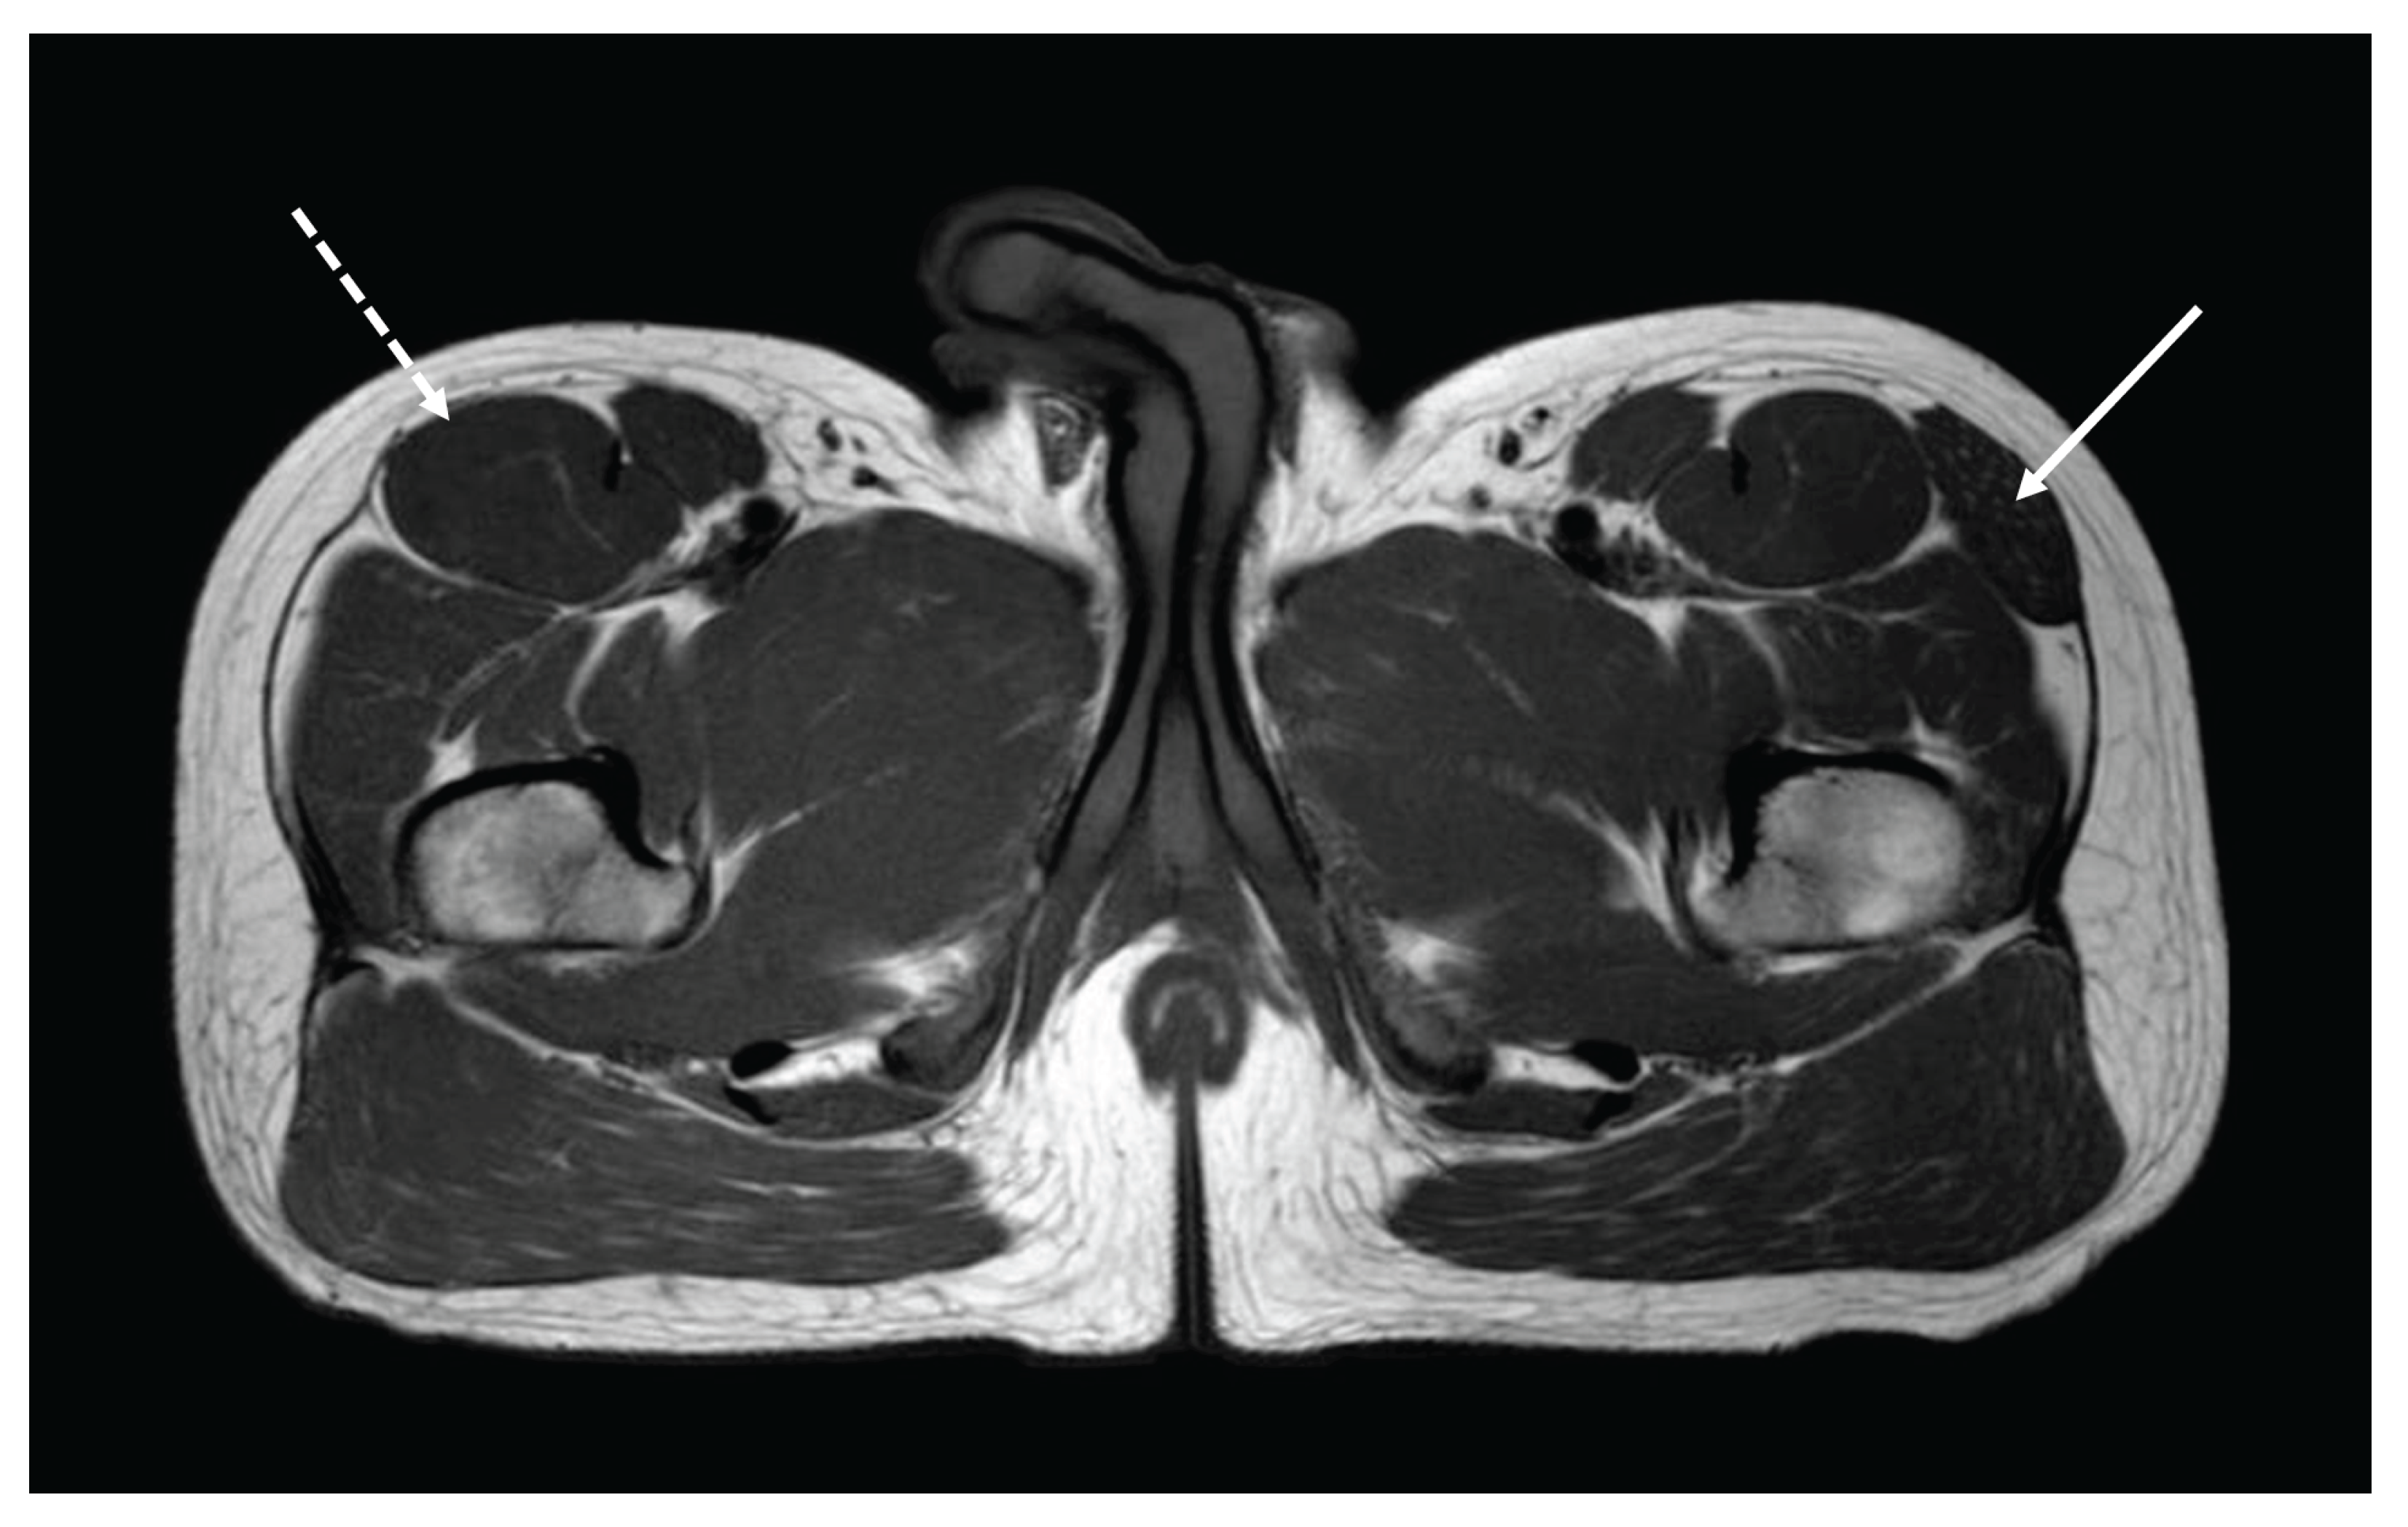

A 25-year-old physician (T.B.) born from non-consanguineous parents was included as a healthy control in a muscle-MRI study conducted by the third author (G.B.) on genetic myopathies as a part of his pediatric residency thesis. T1-weighted axial sections performed at the lower girdle level surprisingly showed the agenesis of the right TFL with mild compensatory hypertrophy of the ipsilateral rectus femoris (dashed arrow) and unaffected surrounding tissues. A normal appearance of the right TFL was noted on the left side (arrow). Muscle MRI was bilaterally normal at thigh and leg levels. The tensor fasciae lata (TFL) is a muscle of the proximal anterolateral thigh that lies between the superficial and deep fibers of the iliotibial (IT) band [